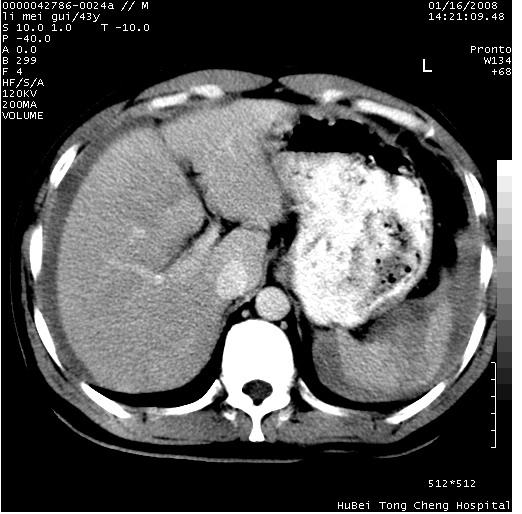

| 患者,男,43岁。突发腹痛2小时,面色苍白,难以平卧。自述近期无明确外伤史,为摩托车驾驶员。 腹部b超检查:脾脏中上极回声异常,肿瘤待排。 临床诊断:腹痛原因待查。 上中腹部ct轴位平扫+增强扫描(层厚10mm,螺距1.0,重建间隔10mm),图像如下: ![]() ![]() ![]() ![]() ![]() ![]() ![]() ![]() ![]() ![]() ![]() ![]() ![]() ![]() ![]() ![]() ![]() ![]() ![]() ![]() ![]() ![]() ![]() ![]() ![]() ![]() ![]() ![]() ![]() ![]() ![]() ![]() ![]() ![]() ![]() zrs发言:支持脾破裂 wwp发言:支持脾破裂并腹水。 xulianj发言:脾脏肿瘤破裂可能性大 zsl6918发言:不像肿瘤出血,考虑还是与外伤后引起的慢性出血有关 zzyy发言:平扫见肝周及脾周积液,脾内密度不均。脾内肿瘤较少见。还是外伤性脾破裂。 沈丘东方医院发言:脾门区一个不均匀强化病灶与其周液体相连多考虑脾占位破裂出血 yixianman001011发言:脾破裂并腹水是可以肯定的,具体原因多以肿瘤性破裂出血,脾脏淋巴瘤可能性大. 结果: 术后,经详细询问患者,其仔细回忆:一月前骑摩托时左侧腰部与别人有“轻微”触碰,因责任在自已,当时又无明显不适,未引起注意。 临床术后诊断:脾破裂并失血性休克(1.外伤性迟发性脾破裂。2.脾脏肿瘤破裂?) 术后标本病检:脾破裂并出血,未见明显肿瘤成份。 原贴地址:http://www.radinet.com.cn/forum_view.asp?forum_id=4&view_id=34070 |